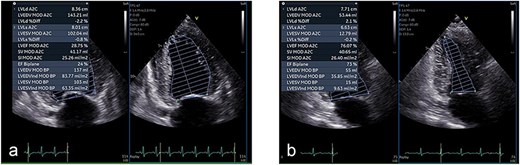

Transthoracic echocardiography showed severe left ventricular systolic dysfunction with a left ventricular ejection fraction (LVEF) of 24% by Simpson’s method (Fig. 2a). Kidney–ureter–bladder radiography and computed tomography performed to investigate systemic causes revealed severe bilateral hydronephrosis due to bilateral impacted ureteral stones (left: 17 × 7 mm; right: 10 × 8 mm; attenuation ~1350 HU) (Fig. 3). Retrograde ureteral stent placement was attempted on the same day but failed because contrast medium could not pass through the obstructed segments (Fig. 4). A left percutaneous nephrostomy (PCN) was therefore performed, followed by right PCN one week later. Concomitantly, guideline-directed heart failure therapy was initiated, including spironolactone (12.5 mg/day), empagliflozin (10 mg/day), sacubitril/valsartan (100 mg/day), and bisoprolol fumarate (1.25 mg/day).

Echocardiographic improvement after urinary decompression. (a) Initial transthoracic echocardiogram showing severely reduced left ventricular systolic function with a Simpson’s ejection fraction (EF) of 24%. (b) Repeat echocardiogram at 3 months showing significant recovery, with EF improved to 73%.

After urinary decompression, heart failure symptoms rapidly improved. At 3 months, BNP had decreased to 212 pg/mL, and LVEF had recovered to 73% (Fig. 2b). The CTR normalized, and body weight decreased by 9.2 kg (Fig. 1b). No infectious complications occurred, and antibiotics were not required. After stabilization of cardiac function, endoscopic treatment of the left ureteral stone was performed 4 months after presentation, achieving stone-free status. The right ureteral stone remained under treatment at the time of reporting; however, bilateral PCN drainage was maintained, and no recurrence of cardiac dysfunction was observed.